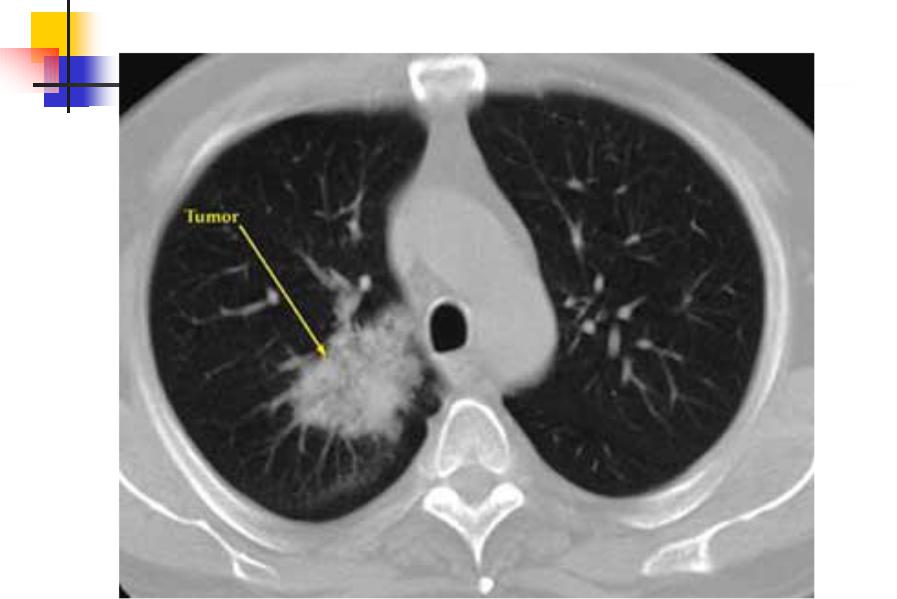

Фотографии и снимки КТ легких без контрастных веществ

Раздел: Визуальный дайджест